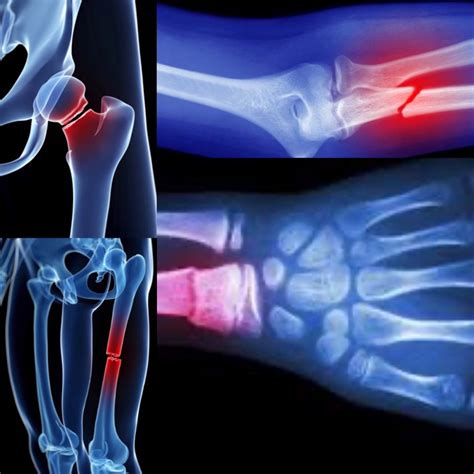

I traumi che coinvolgono le ossa e le articolazioni possono variare in gravità:

- Distorsione: Si verifica quando un'articolazione subisce un allungamento o uno strappo dei legamenti, le fibre che connettono le ossa tra loro. Questo può causare dolore, gonfiore e limitazione del movimento.

- Frattura: Consiste nella rottura di un osso. Le fratture possono essere complete (l'osso è diviso in due o più frammenti) o incomplete (l'osso è lesionato ma non completamente spezzato). La gravità e il tipo di frattura dipendono dalla forza dell'impatto e dalla resistenza dell'osso.

- Lussazione: È una lesione più grave in cui le estremità delle ossa in un'articolazione vengono completamente separate dalla loro posizione normale. Spesso le ossa non rientrano spontaneamente nella loro sede, richiedendo un intervento medico per la riduzione.